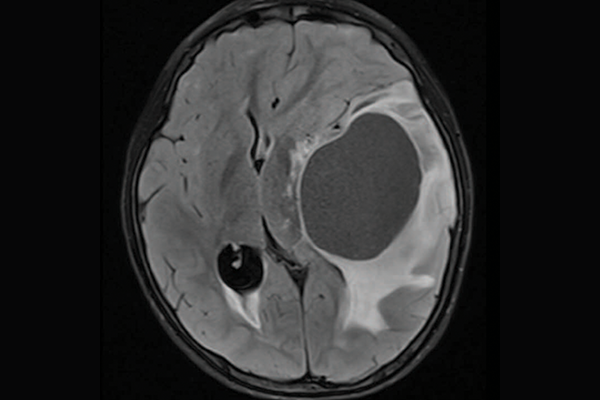

A scan of a brain with priMMRD subtype 2

priMMRD-2: The double agent

These tumours account for 19 per cent of the gliomas studied and have MMRD mutations without PPD or IDH1 gene alterations. For these patients, a single-agent immunotherapy is less effective, but adding a second agent may improve outcomes. The OPTIMISE trial, led by Dr. Daniel Morgenstern at SickKids, is using an adaptive trial design to target these specific genetic variations.